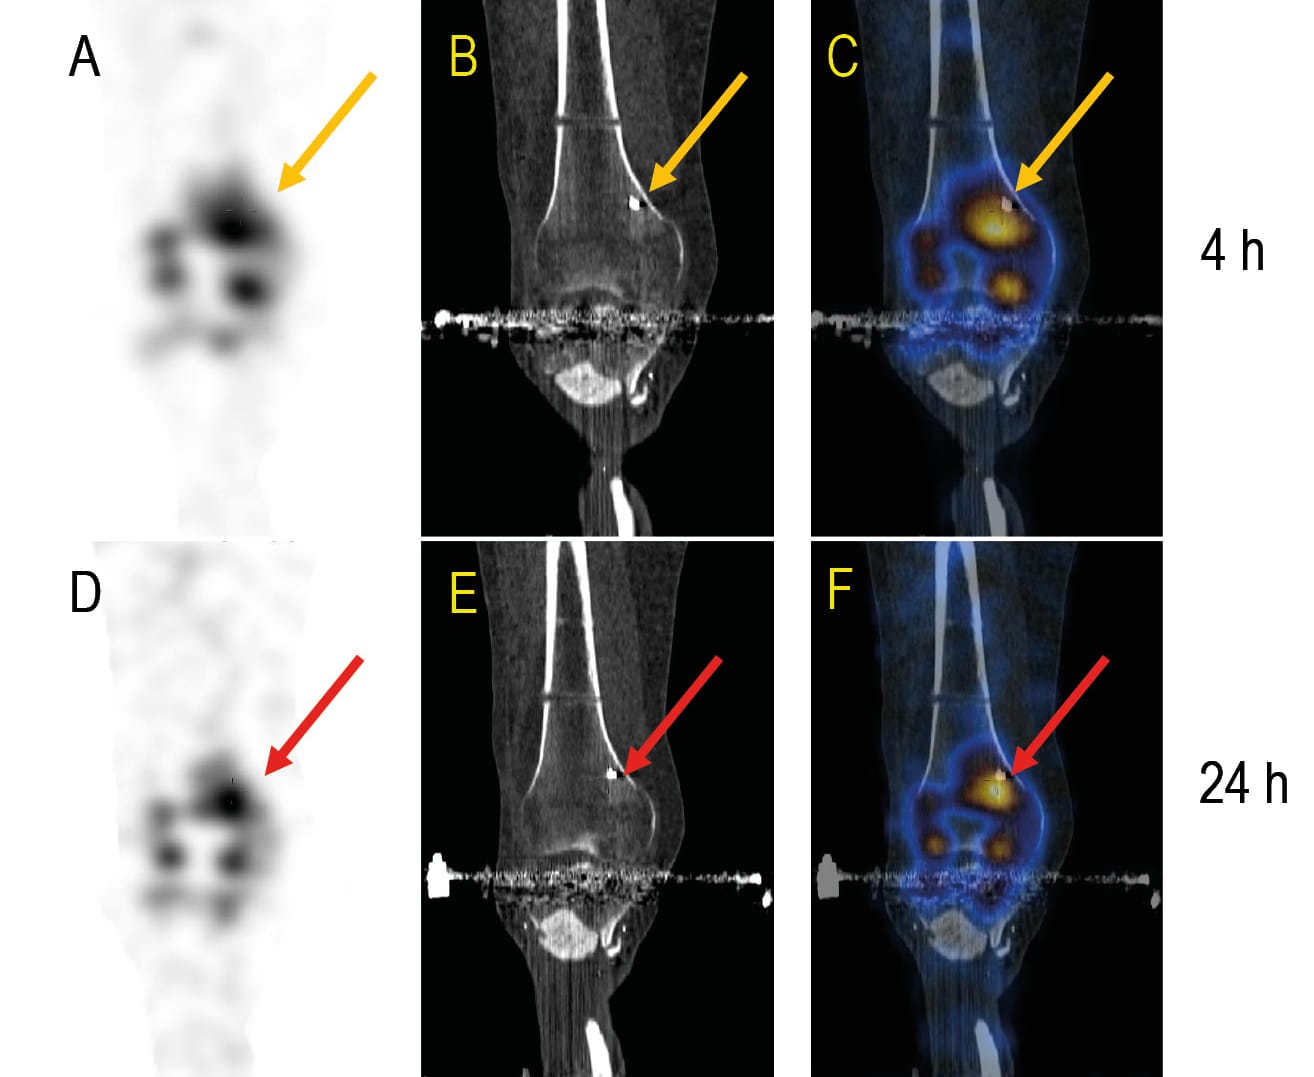

To better visualise the value of these examinations, please refer to Figures 1 to 3. Figure 1 shows a photo of a patient. It shows multiple injuries to the lower extremities with many small, seemingly non-irritant wounds and treatment with an external fixator. Figure 2 shows the corresponding radiograph of the right lower leg with the knee joint. Multiple small radiopaque foreign bodies can be seen. Figure 3 shows the evaluation using anti-granulocyte antibody SPECT/CT. It is very easy to recognize which foreign bodies accumulate granulocytes in their surroundings. This corresponds to an infection. Many other foreign bodies do not have this accumulation and are therefore not infected.

In most cases, the patients had multiple injuries. In many cases there were chronic wounds and older fractures. Anti-granulocyte antibody (AGA) scintigraphy and SPECT/CT examinations were used in these cases in order to be able to reliably distinguish between Post-traumatic osteomyelitis (PTO), also known as ‘fracture-related’ osteomyelitis with increased AGA uptake and non-specfic changes in the case of ambiguous wound conditions. For treatment planning, it was also important to know which fragments of the fractures were avital in order to remove them and thus eliminate a possible reservoir for bacteria. For this purpose, we used 18F sodium fluoride (Na[18F]F) PET/CT examinations to detect avital bone fragments.

In an animal experiment with small, injected fragments, the authors were hardly able to find any relevant changes on the skin surface in many cases [2] Bowyer GW, Cooper GJ, Rice P (1995) Management of small fragment wounds in war: current research. Ann R Coll Surg Engl 77:131-134. This is consistent with our experience that, particularly in the case of blast injuries, the skin over the blasted foreign bodies often shows no evidence of infection. In order to clarify the question of which injuries we should treat surgically first, imaging - especially nuclear medicine imaging - was of great value to us. Even though the initial screening and the first debridements gave us a good picture of the extent of the infections and the infected regions at an early stage, this imaging repeatedly gave us indications of unknown centres of infection or possible reservoirs for germs in avital bone areas.

Due to the high sensitivity and specificity for peripheral bone infection with hardware in situ granulocyte or leucocyte scintigraphy with SPECT/CT is recommended for this indication in current European consensus papers [5] Glaudemans A, Jutte PC, Cataldo MA et al. (2019) Consensus document for the diagnosis of peripheral bone infection in adults: a joint paper by the EANM, EBJIS, and ESR (with ESCMID endorsement). Eur J Nucl Med Mol Imaging 46:957-970.